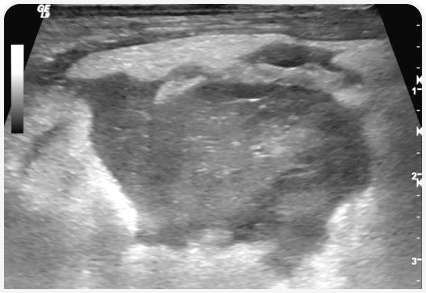

Наиболее распространенным методом визуальной диагностики, используемым для оценки состояния поджелудочной железы у собак, является ультразвуковое исследование брюшной полости.

Изменения, наблюдаемые при остром панкреатите, включают в себя увеличение размера и гипоэхогенную структуру поджелудочной железы, часто с гиперэхогенной перипанкреатической областью брыжейки (Рисунок 3).

Также могут выявляться сопутствующие аномалии, такие как псевдокисты, абсцессы или опухолевые образования поджелудочной железы, а также выпот в брюшную полость (6, 11, 17).

В поджелудочной железе могут обнаруживаться гиперэхогенные зоны, что может быть обусловлено фибротическими изменениями ткани (12). Однако УЗИ брюшной полости как единственный метод диагностики острого панкреатита у собак, как правило, имеет низкую чувствительность, по результатам одного исследования составляющую около 68 % (11).